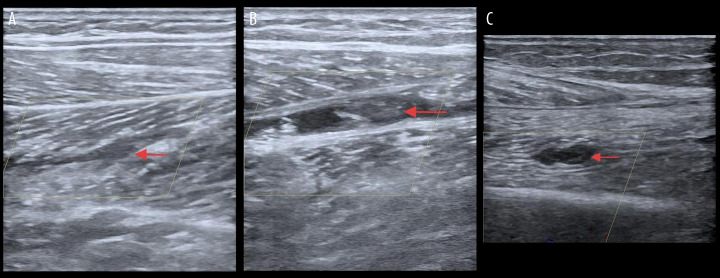

BACKGROUND Conventional clinical understanding holds that venous thrombus formation typically occurs days after traumatic injury. However, our findings demonstrate that acute thrombosis can begin within 7.5 hours after fracture in knee trauma cases, challenging existing paradigms. CASE REPORT A 43-year-old man was admitted to the Emergency Department (ED) after an electric bicycle accident precipitated by acute-onset dizziness accompanied by visual disturbances. Initial radiographic evaluation confirmed a comminuted right proximal tibia fracture with concomitant multiple acute ischemic cerebral infarctions on neuroimaging. Compression ultrasonography performed in the ED showed no evidence of deep venous thrombosis in the lower extremities. However, markedly elevated D-dimer levels (9.39 mg/L; reference <0.5 mg/L) prompted high clinical suspicion for occult venous thromboembolism. Serial Doppler ultrasound surveillance revealed the rapid development of a free-floating thrombus in the right soleal vein within 7.5 hours after the fracture occurred. CONCLUSIONS This case report documents the exceptionally rapid development of venous thrombosis within 7.5 hours following a proximal tibia fracture, particularly in high-risk patients with comorbid conditions such as diabetes mellitus and ischemic stroke. These findings necessitate immediate reassessment of current thromboprophylaxis protocols in orthopedic trauma, emphasizing the critical importance of early and frequent vascular monitoring (including serial Doppler ultrasonography and D-dimer assessment) to detect hyperacute thrombus formation. Clinicians must maintain heightened awareness of this emergency thromboembolic risk while simultaneously managing hemorrhage concerns, as this case demonstrates that the traditional 24-hour prophylaxis window may be inadequate for certain high-risk trauma populations.